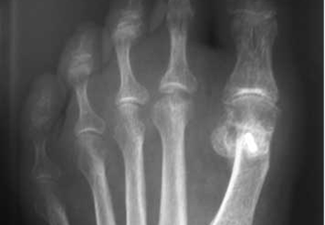

Hallux Valgus Falangico. La desviación se encuentra en el dedo y no en la articulación.

Observese la rotación que dificulta el calzado.

Dedo torcido. Imagen radiográfica con deformidad en la primera falange.